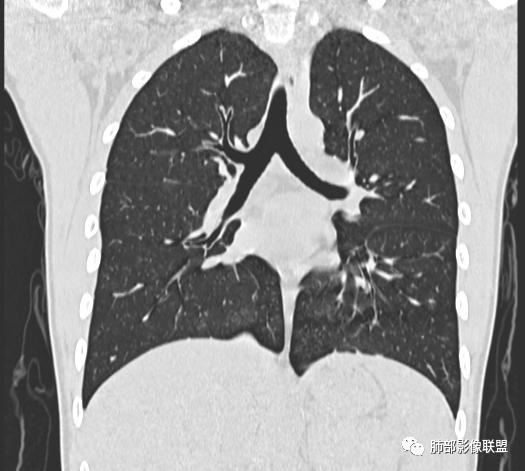

小强:青年,发热,皮疹;双肺散在结节,周围磨玻璃,点晕征,疱疹病毒感染,鉴别荚膜组织胞浆菌,结核。 大雄:青年,急性起病,发热伴全身皮疹2天,抗病毒治疗体温有下降。双肺随机分布大小不等类圆结节,“点晕征”。考虑水痘-疱疹病毒(VZV)血播询问接触史,查体皮疹分布以及形态基本可诊断。 王开金江津中心医院呼吸科:青年男性,起病急,病程短,以发热,皮疹为首发症状,感染指标以单核细胞升高为主,胸部ct双肺多发结界,周围有晕,点晕表现,随机分布,同意於老师意见,水痘疱疹病毒血流感染累及肺。 王秀仙:双肺多发大小不等结节,周围有晕,边缘模糊,呈点晕征表现。青年,急性起病,发热伴全身皮疹2天,抗病毒治疗体温有下降。考虑疱疹病毒。鉴别荚膜组织胞浆菌。 傅昌瑜:19岁男性,发热、全身皮疹2天,单核细胞增高,双肺多发结节,结节边缘见边界不清磨玻璃影。点晕征+发热、全身皮疹+单核细胞增高——考虑水痘-带状疱疹病毒肺炎。 一切∮随缘:年轻男性,发热,皮疹两天,实验室,CRP,PCT增高,影像:双肺多发散在磨玻璃结节,边界欠清,大小不等,呈点晕征改变,以血管束周围分布为主,局部血管束略增粗,其它无明显改变,考虑:1:病毒性肺炎(水痘疱疹病毒?不知道皮肤有无改变)2:真菌(组织胞浆菌,血管侵袭性肺曲霉)3:GPA4:寄生虫(实验室没有看到嗜酸细胞增高) 赵山河:双肺散在结节,周围有晕,边缘模糊,呈点晕征表现。青年,急性起病,发热伴全身皮疹2天,抗病毒治疗体温有下降。考虑水痘—疱疹病毒感染。洪桥爱:青年男性,发热、皮疹2天,伴瘙痒,皮疹于面部首发,之后进展至全身,虽然没有对皮疹进行描述,但是从出疹时间及皮疹进展情况,伴瘙痒,应该就是个水痘患者;CT提示双肺随机分布结节影,部分结节伴有边界不清晕征,考虑水痘血播肺。 刘强:年轻男性,急性起病,皮疹,发热,抗感染治疗体温下降,说明有效。影像表现为散在点晕征,感染类疾病谱(疱疹病毒,真菌,结核),结合年龄,皮肤皮疹,考虑水痘-疱疹病毒性肺炎。 小兜:男性,19岁,发热皮疹两天,颜面部至全身,CRP,降钙素及单核增高。CT示双肺散在小结节,周围伴磨玻璃影,点晕征,考虑为水痘-带状疱疹病毒(varicella-zoster virus,VZV)肺炎 必有路:青年,皮疹+发热+“点晕征”→水痘-疱疹病毒(VZV) 许慧良:青年男性患者,发热、皮疹2天,体温最高38.5℃,第3天皮疹扩展至全身,伴瘙痒,胸部CT:双肺多发随机分布的小结节,结节周边见边界模糊的晕征,考虑水痘病毒感染流心明智:男,19,急性起病,发热伴全身皮疹2天。出疹顺序头→全身,抗病毒有效。胸部CT:两肺多发大小不等类圆形实性小结节影,随机分布,结节周围环绕GGO,边界模糊,呈点晕征。出疹特点是关键,未提示。考虑:血播病毒性肺炎,水痘-疱疹病毒?麻疹?鉴别荚膜组织胞浆菌、TB、血管炎、寄生虫等。 浪迹天涯:病灶多为5-10mm大小结节,结节周围可见磨玻璃样的晕环,常多发,可分布于肺内任何区域,考虑水痘—带状疱疹病肺炎如果短时间内有新的一个区域浸润,更加能说明,